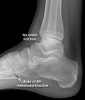

X-ray : 제5중족골 골절(Avulsion fracture of Plantar fascia)

X-ray : 제5중족골 골절(Avulsion fracture of peroneus brevis tendon)